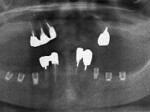

両側5歯症例

両側5歯症例両側5歯症例両側5歯症例 主訴-義歯のバネが壊れて手前の歯が痛んできた。 術前(旧義歯装着、鏡像) 術前(下顎粘膜面、鏡像)術前(下顎粘膜面、鏡像)術前(下顎粘膜面、鏡像) 術前レントゲン術前レントゲン術前レントゲン 術前口腔内(正面観)術前口腔内(正面観)術前口腔内(正面観)

術後(鏡像)術後(鏡像)術後(鏡像) 術後口腔内(正面観)術後口腔内(正面観)術後口腔内(正面観)もう入れ歯は要らなくなりました。 術後レントゲン術後レントゲン術後レントゲン